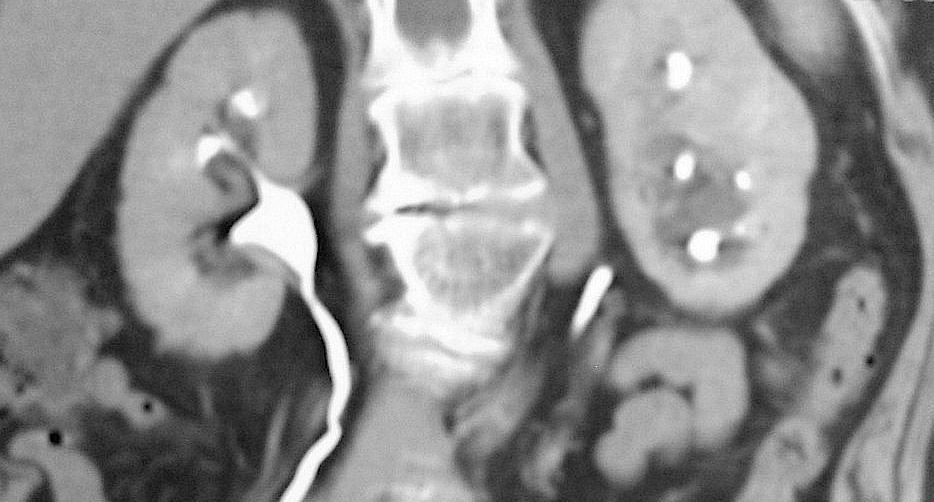

Case Discussion. A column of Bertin is the extension of renal cortical tissue which separates the pyramids, and as such are normal structures. They become of radiographic importance when they are unusually enlarged an may be mistaken for a renal mass ( renal pseudotumor ).. Hipertrofia de columna de Bertin: crecimiento anómalo de la cortical hacia el seno renal, que puede simular una masa sólida. Se produce entre el tercio medio y superior renal (fig. 1B).-Lobulación fetal: se diagnostica cuando la superficie del riñón presenta un marcado abombamiento, sin alteración en la anatomía renal corticomedular.-

La columna renal (o columna de Bertin, o columna de Bertin) es una extensión medular de la corteza renal entre las pirámides renales. Permite que la corteza esté mejor anclada. Una columna renal hipertrofiada (o pseudotumor renal) se puede diferenciar de un tumor renal real con la ayuda de una gammagrafía con DMSA. La exploración mostrará el área con actividad normal si se trata de un.. A: colocación de la sonda e imágenes ecográficas en los 2 cortes típicos de la exploración del aparato urinario. B: riñón en longitudinal con hipertrofia de columna de Bertin. C: riñón en transversal con quiste cortical. D y E: riñón con quistes sinusales en corte longitudinal y transversal.